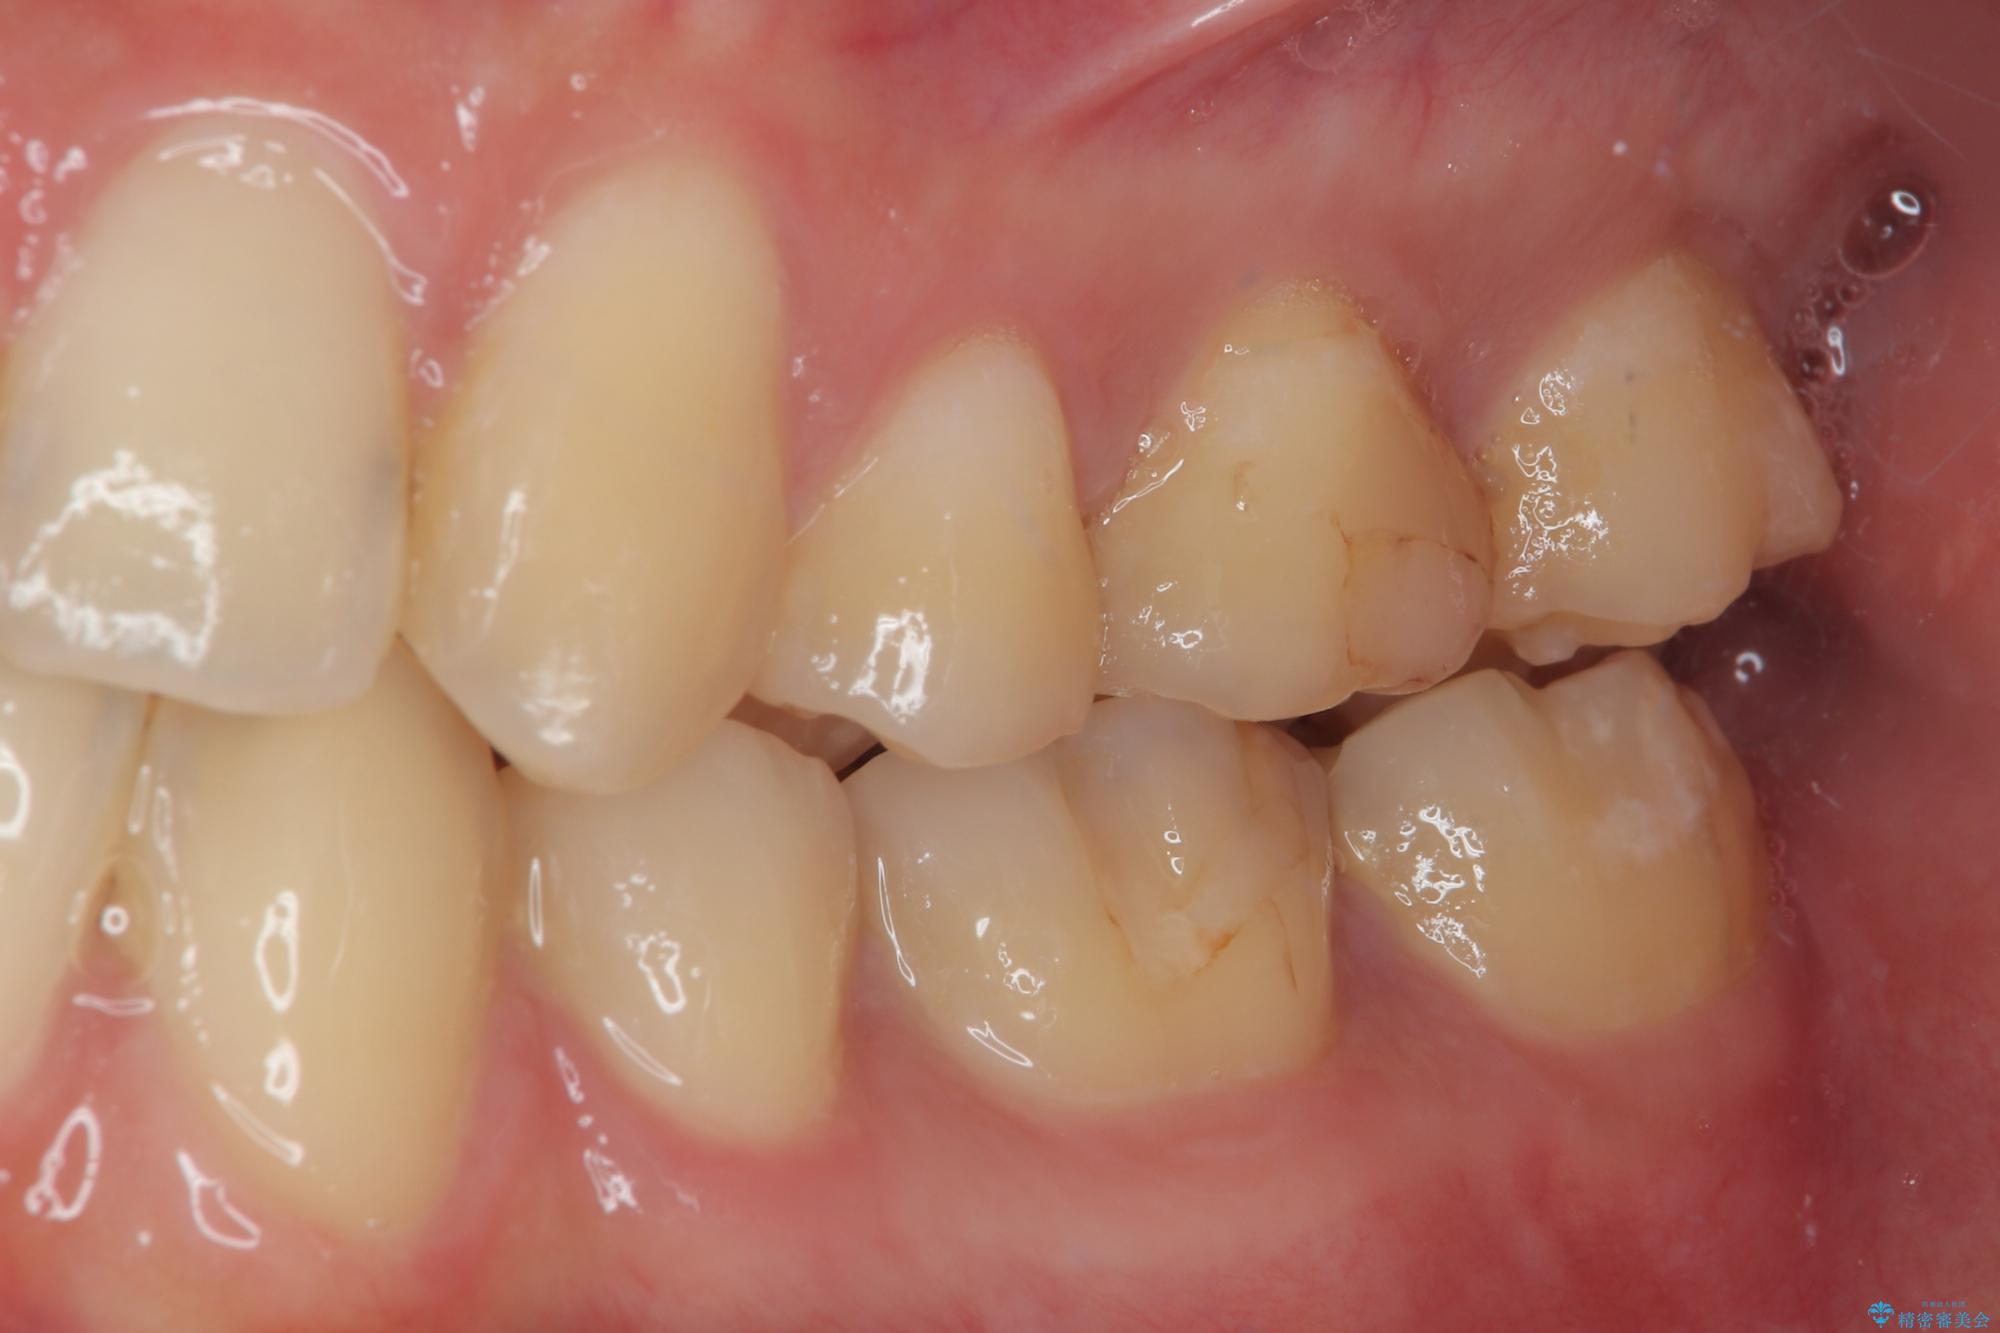

虫歯による不快な症状がなくなり喜んでいただきました。セラミックの被せものが入った後の違和感なく過ごせているそうです。矯正治療終了直後の被せもの治療なのでリテーナーの作成回数をできるだけ少なく迅速に行うことを考慮して治療を行いました。

今後、ホワイトニングを行う予定なので、患者様のご希望により、周りの歯に比べてあえて白い被せものを作成しました。